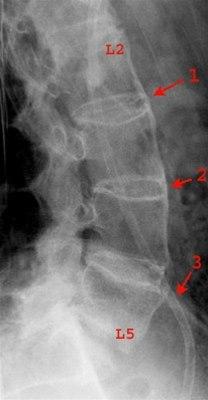

Røntgen- og MR-undersøkelser

Røntgenundersøkelse av ryggsøylen kan vise karakteristiske skjelettforandringer i korsryggen. De typiske funnene ses oftest i overgangen mellom lendevirvlene og bekkenknoklene, i det som betegnes iliosakralleddene (IS-leddene). Noe sjeldere ses forandringer i rommet mellom lendevirvlene.

Ofte må sykdommen ha pågått i flere år før skjelettforandringene blir synlige ved vanlig røntgenundersøkelse. I tidlig fase kan det derfor være aktuelt å foreta mer avanserte bildeundersøkelser, vanligvis MR, hvor forandringene kan påvises tidligere.

I tidlig sykdomsfase forventes ikke funn på røntgen slik at praksis ofte blir at man tar både MR- og røntgen av IS-ledd. Dersom MR ikke kan gjøres, er CT av IS-leddene et alternativ.

Hvis bildeundersøkelsene er negative, men mistanken om betennelse i ryggsøylen vedvarer, anbefales å ta nye bilder etter noen år.